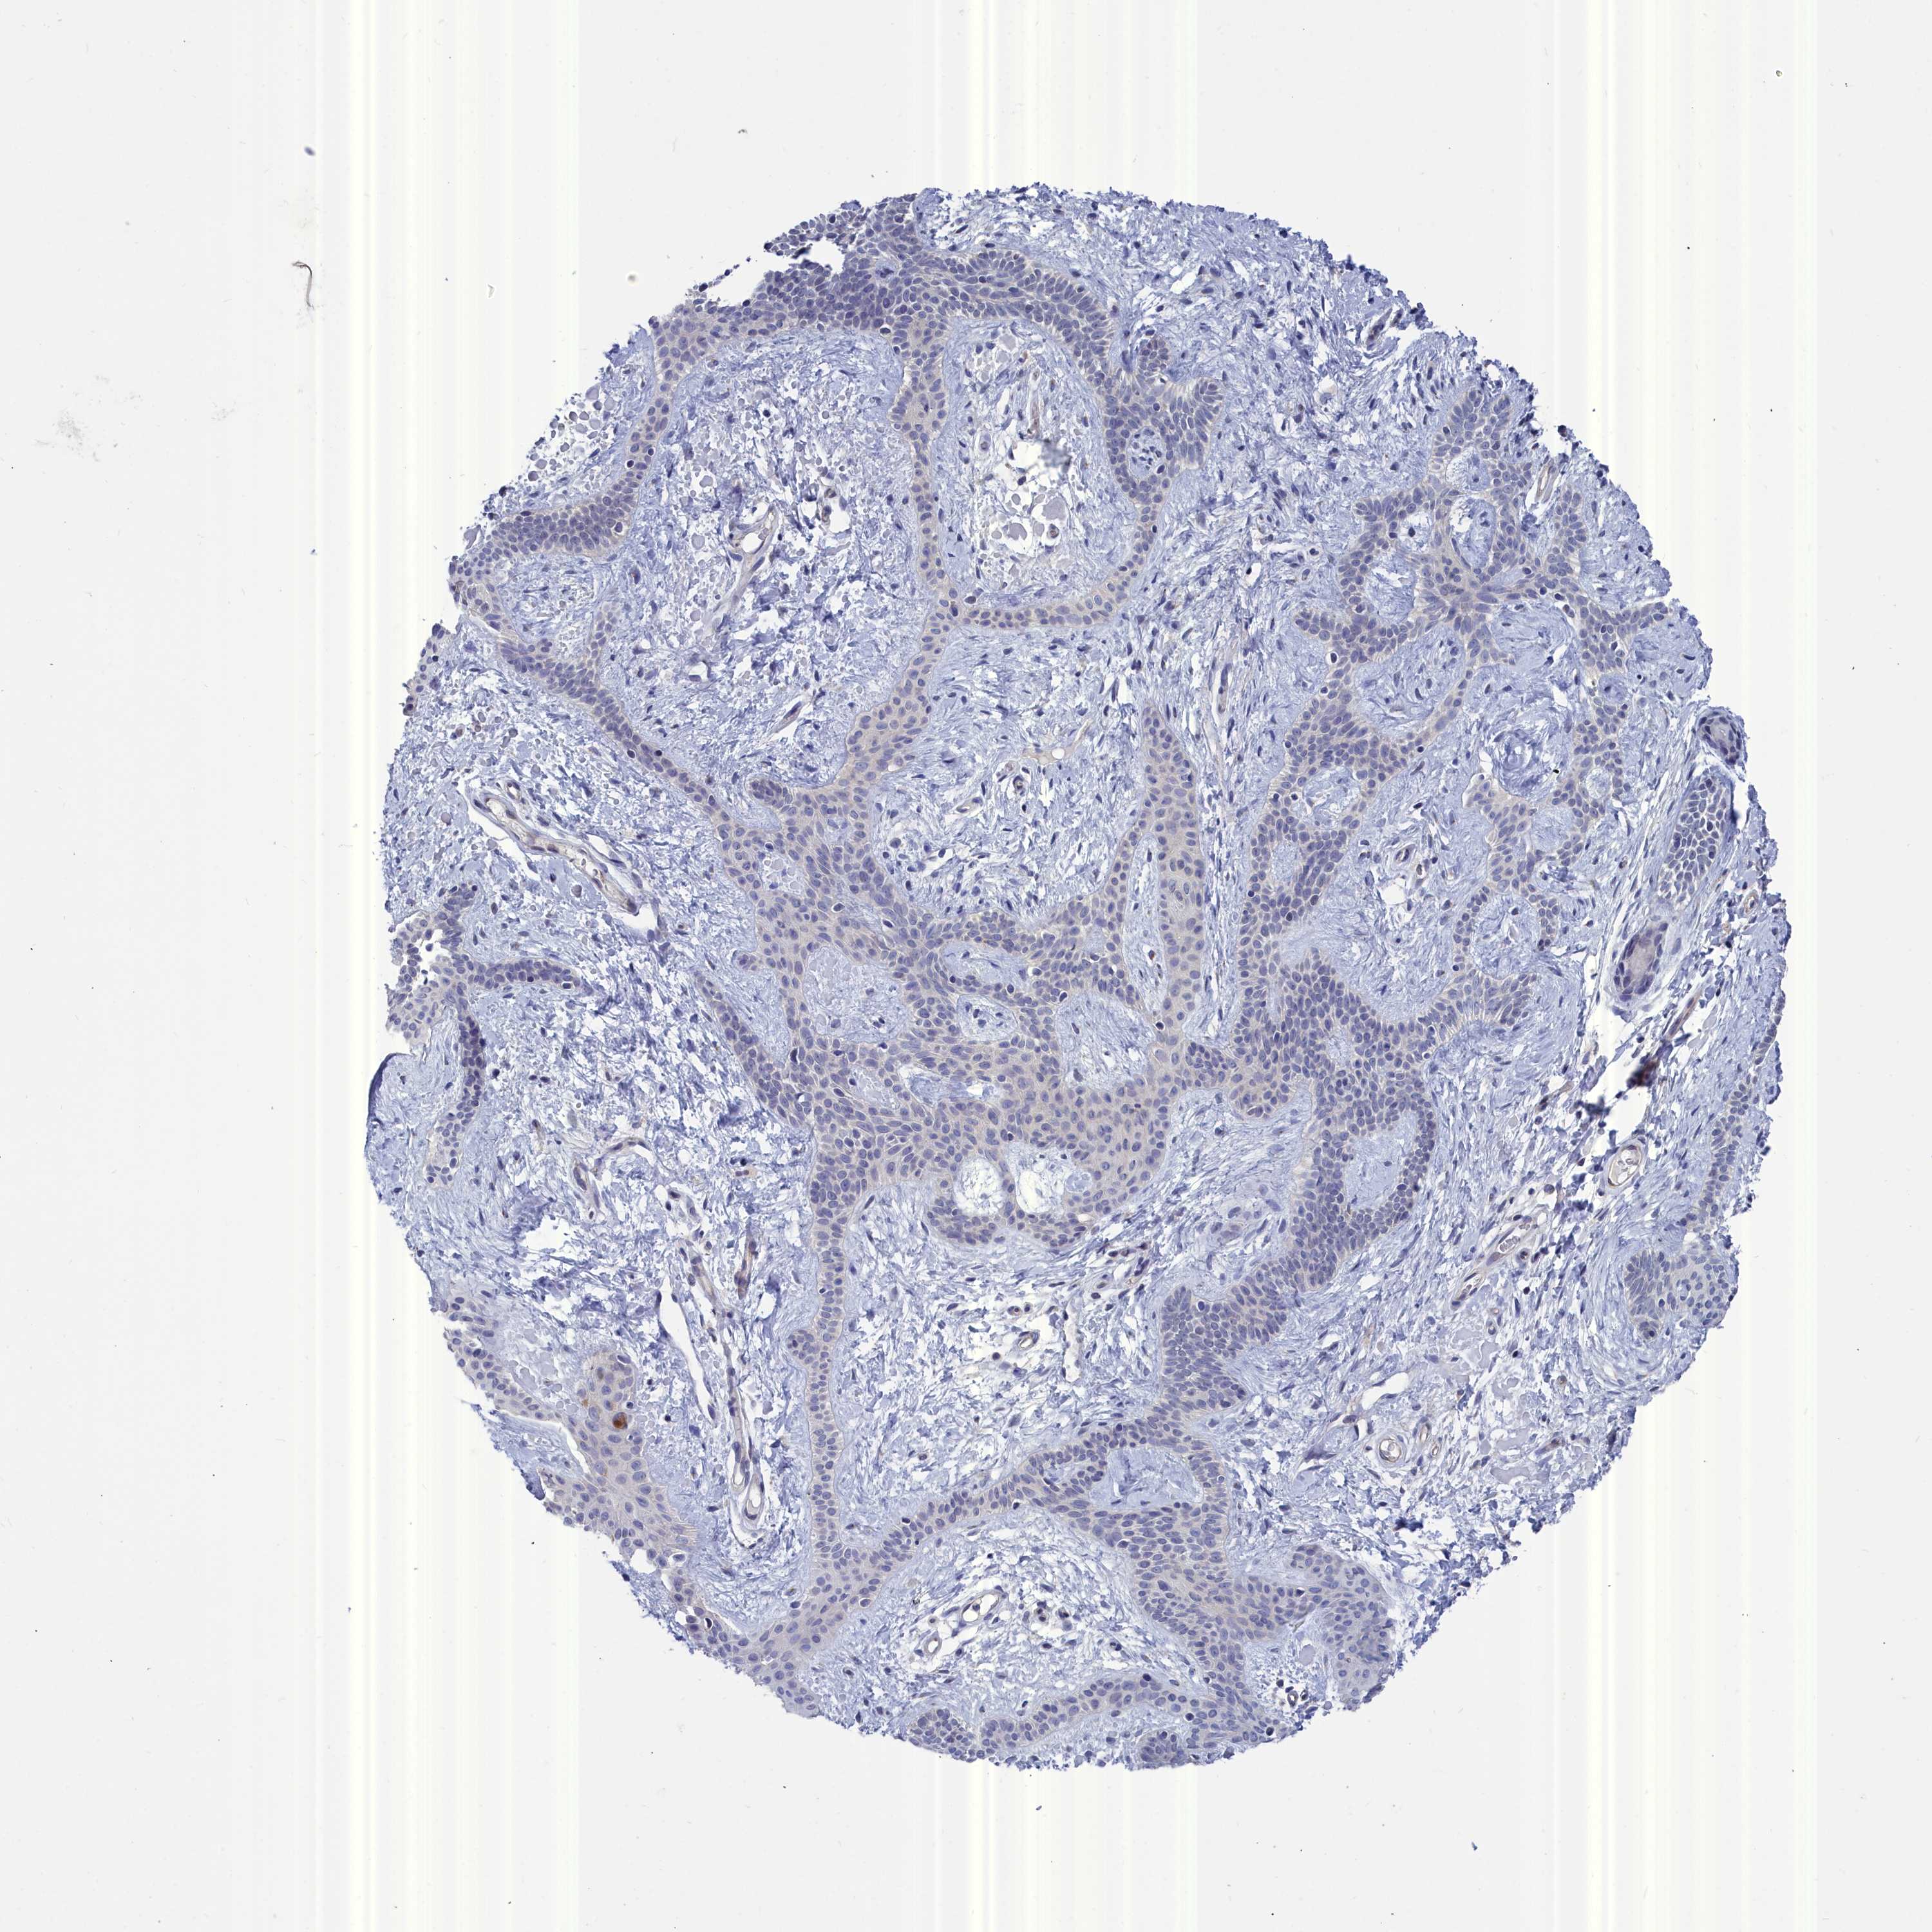

SKIN CANCER - Protein expressioni

A mouse-over function shows sample information and annotation data. Click on an image to view it in a full screen mode. Samples can be filtered based on level of antibody staining by selecting one or several of the following categories: high, medium, low and not detected. The assay and annotation is described here.

Antibody staining in the annotated cell types in the current human tissue is reported as not detected, low, medium, or high, based on conventional immunohistochemistry profiling in selected tissues. This score is based on the combination of the staining intensity and fraction of stained cells.

Each image is clickable and will lead to virtual microscopy that enables deeper exploration of all samples and also displays staining intensity scores, fraction scores and subcellular localization as well as patient and tissue information for each sample.

Antibody HPA000263

Staining

High

Medium

Low

Not detected

Intensity

Strong

Moderate

Weak

Negative

Quantity

>75%

75%-25%

<25%

None

Location

Nuclear

Cytoplasmic/membranous

Cytoplasmic/membranous,nuclear

Squamous cell carcinoma, NOS

Basal cell carcinoma

Squamous cell carcinoma, metastatic, NOS